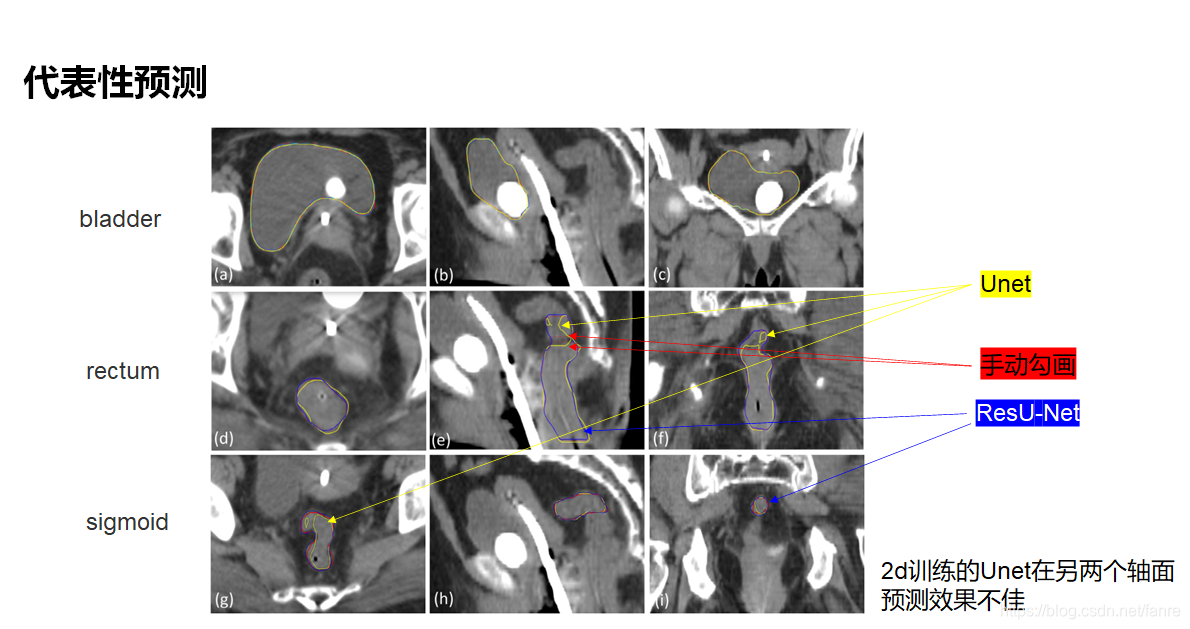

基于深度学习的宫颈癌高剂量率后装放疗危及器官自动勾画

基于深度学习的宫颈癌高剂量率后装放疗危及器官自动勾画